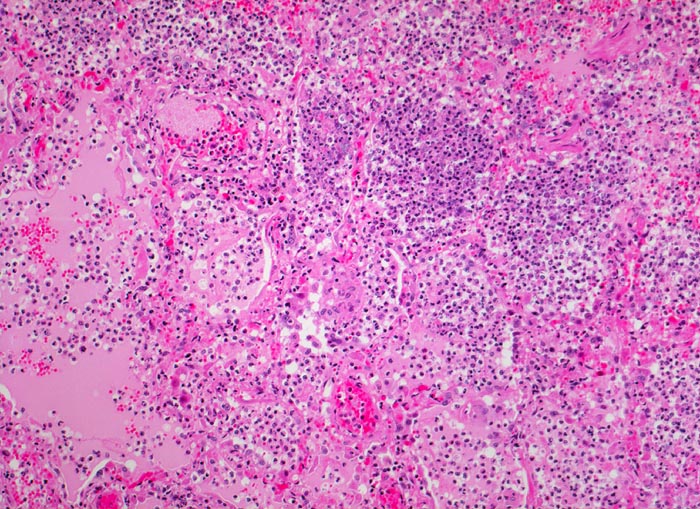

PathoPic – image database / PathoPic ID 4650 - Bronchopneumonie: pneumonisches Infiltrat

Bronchopneumonie: pneumonisches Infiltrat

Pneumonisches Infiltrat: die Alveolen sind gefüllt mit neutrophilen Granulozyten und rosafarbener Ödemflüssigkeit. Die Alveolarkapillaren sind hyperämisch.

Ödem und Gefässhyperämie sind Zeichen der akuten Entzündung und nicht Ausdruck einer akuten Lungenstauung.